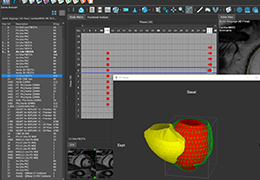

ANYTHINK 经导管主动脉瓣膜置换术分析系统